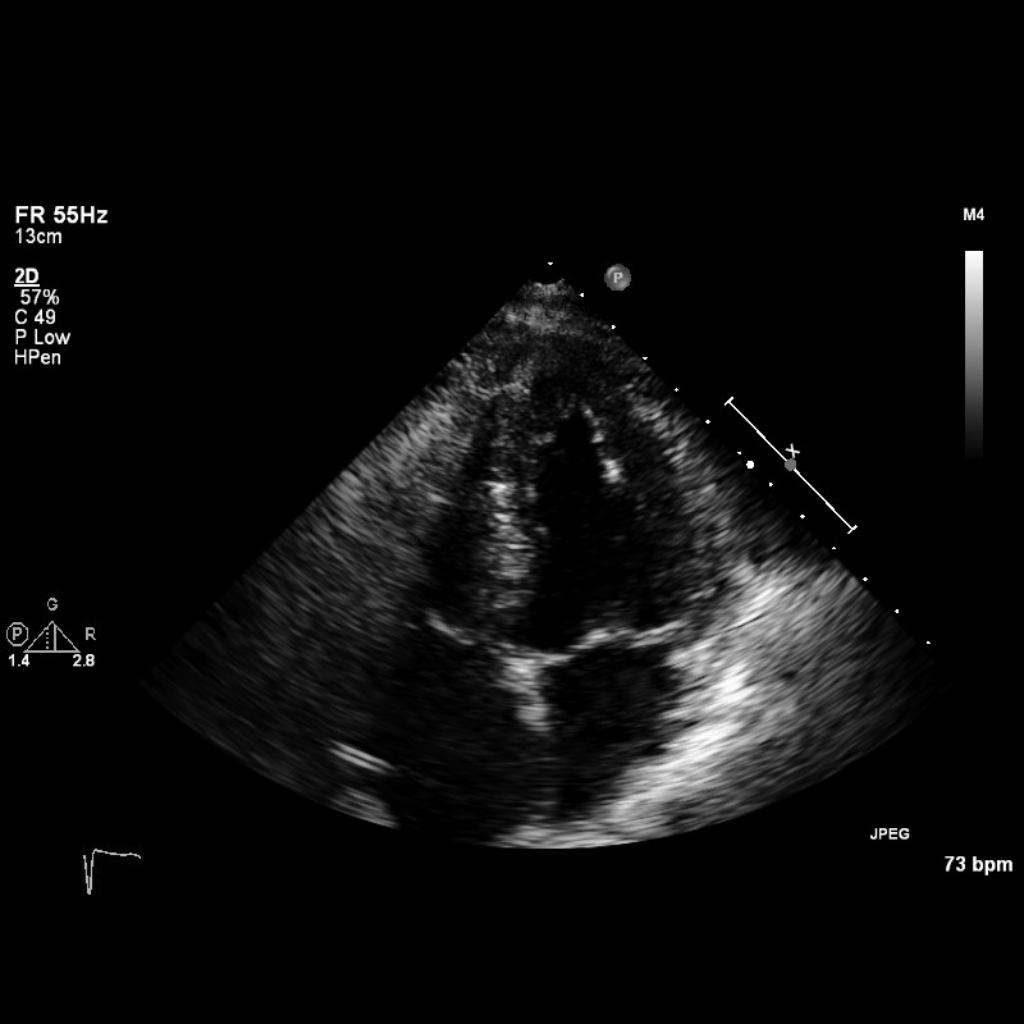

Fig. 1 A sample image from the Unity dataset.

Three echocardiographic datasets were used for experimentation: CAMUS, Unity, and Consensus.

Unity dataset:

Private dataset of 1,224 apical four-chamber echocardiogram videos from Imperial College Healthcare NHS Trust’s database.

Ethically approved (IRAS ID 243023). Contains 2,800 labelled images (70% train, 15% validation, 15% test). -